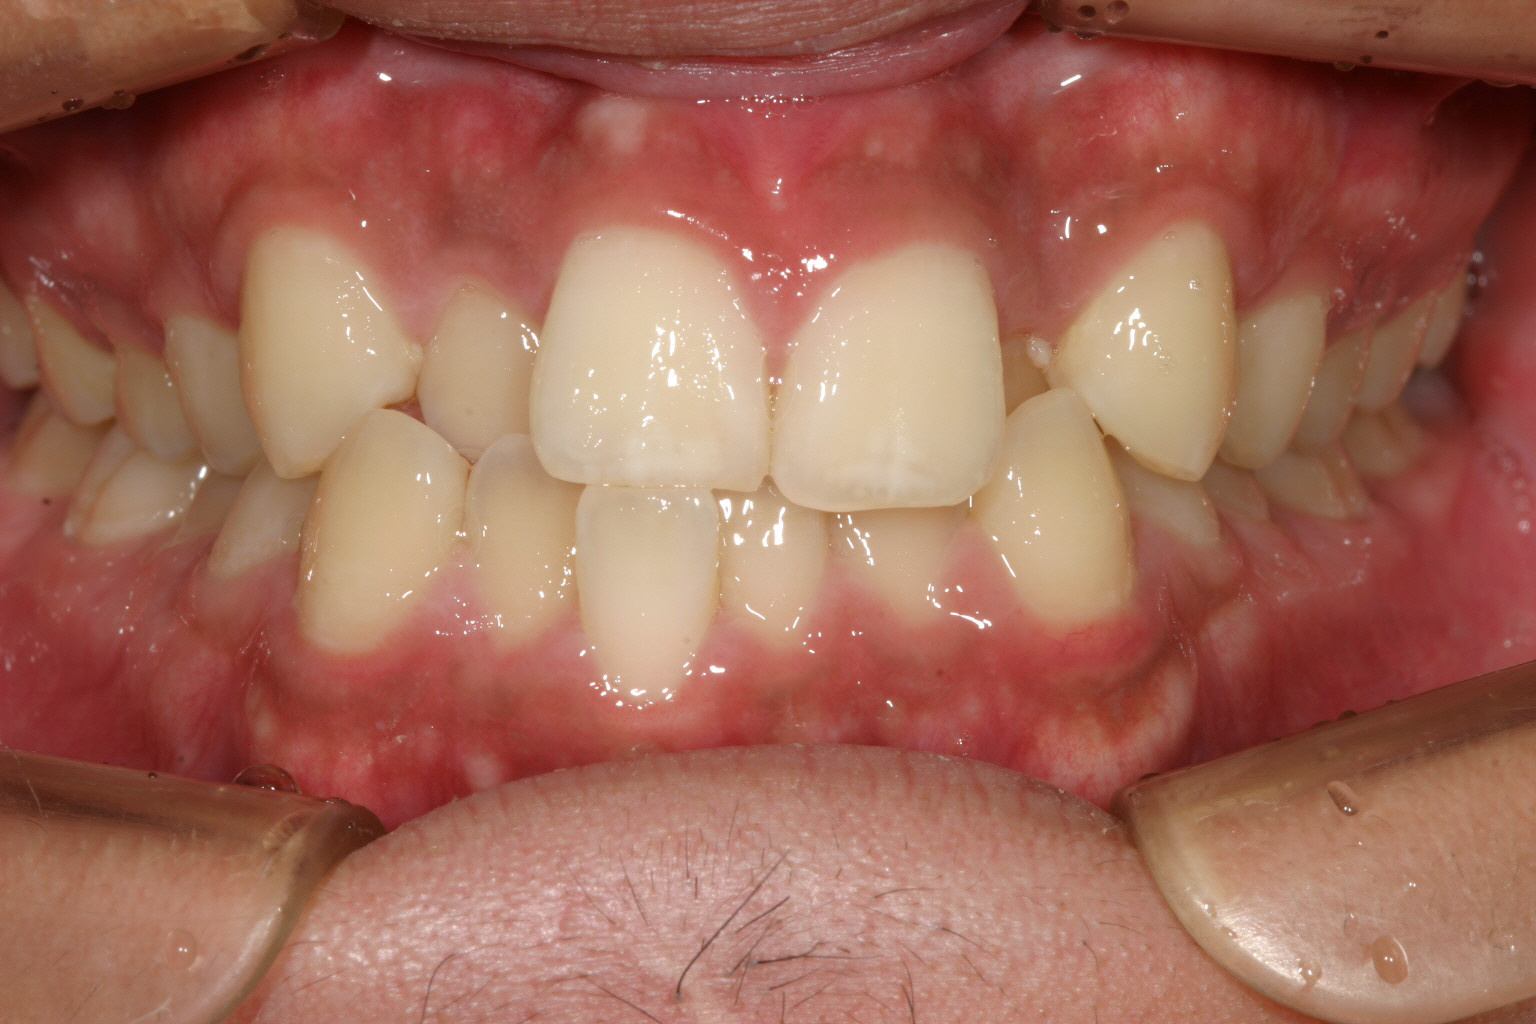

前歯のガタガタが気になるのと物がつまり易い。

歯列弓が狭い為に前歯が並ばずガタガタしています。

下顎もアーチが狭い為叢生になっています。

横から見ると少ししゃくれ気味です。

今回のケースは前歯のガチャ改善を希望されて来院されました。

当院ではよくあるケースで犬歯間が狭くなっている為上手く前歯が並んでいません。